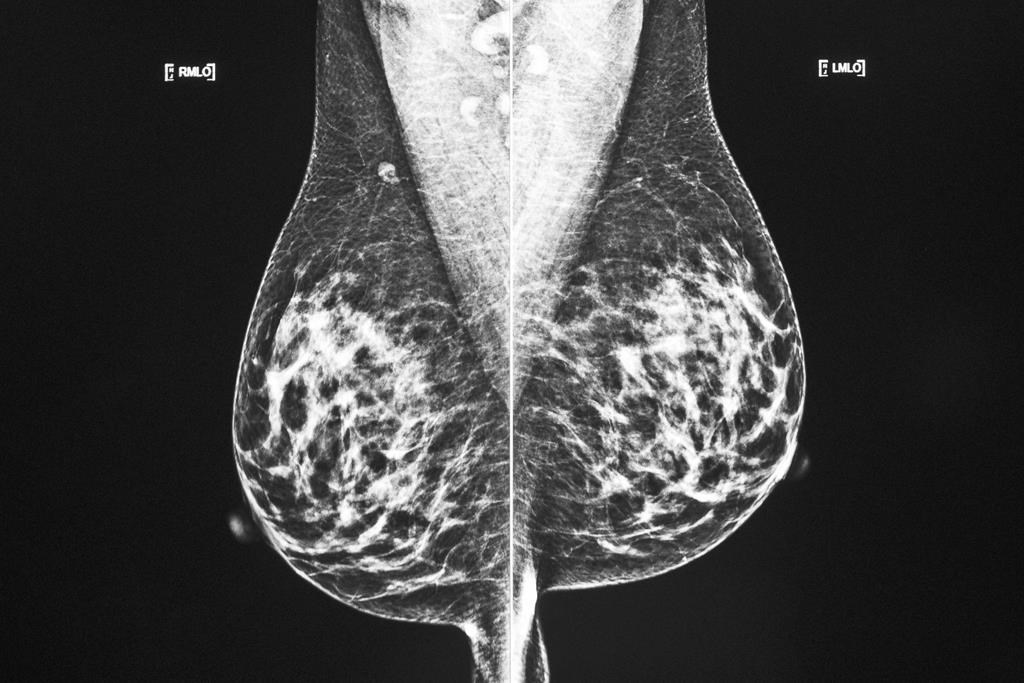

Les taux d'incidence du cancer du sein sont relativement stables et les taux de mortalité sont en baisse, a déclaré M. Brenner.

«Cela est dû en grande partie au succès des approches de dépistage par mammographie dans le cadre de programmes de dépistage organisés, ainsi qu'à l'amélioration des options thérapeutiques au fil des ans», a-t-il expliqué.